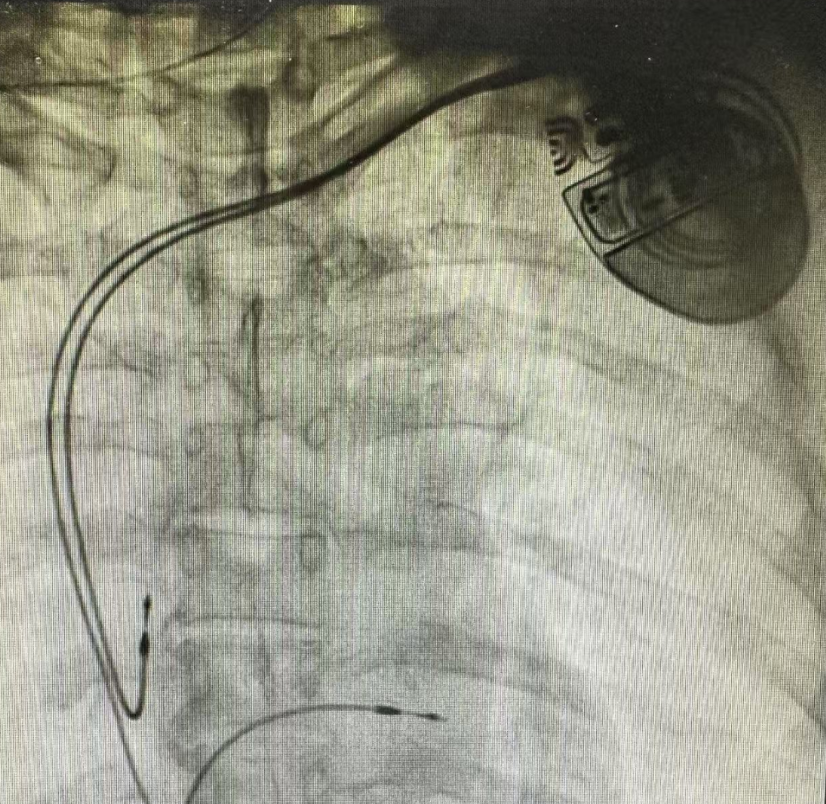

心脏,是人体最勤勉的“永动机”。但当它的电信号传导出现障碍,生命节奏便可能陷入危险的“卡顿”。近日,日照市康复医院心血管团队通过精准植入永久性心脏起搏器,为一位饱受10年胸闷心悸困扰的患者按下“重启键”,让她的心跳重新稳健有力。这场与时间的赛跑,背后藏着怎样的生命故事?

房室传导阻滞是常见心律失常,若患者出现头晕、乏力、黑矇甚至晕厥,需警惕严重心动过缓。动态心电图监测和心脏电生理检查是诊断关键,而永久起搏器能有效预防猝死风险。